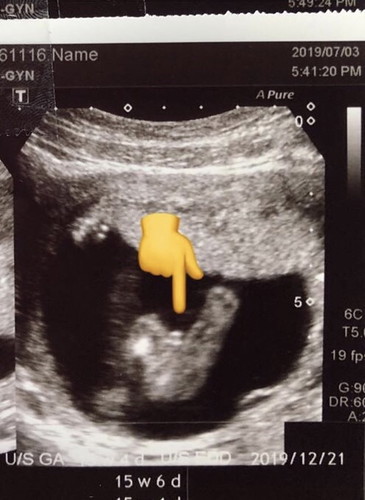

ช่วยดูหน่อยผญ หรือ ผช คะ

แบบนี้ผู้หญิงหรือ ผู้ชายคะ หมอบอกว่าน้องมีกระจู๋ แต่ไม่ได้บอก 100% เพราะอายุครรภ์ยัฃน้อยยุค่ะ

น่าจะชาย ถ้าหญิงจะไม่มีนูน